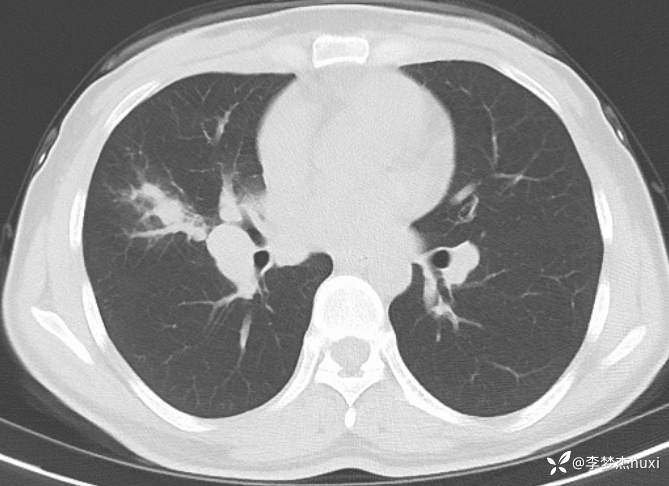

女性35岁,主因咳嗽、咳痰1月,胸部CT报肺炎,猜对乃神医!

女, 35 岁,主因咳嗽、咳痰1月于2025-11-05 08:46入院。

1.现病史:患者中年 女,患者于入院前1月“感冒”后出现咳嗽、咳痰,为黄白痰,不易咳出,无痰中带血,咽部刺痒不适,咳嗽明显,无胸痛,无胸闷、憋气,无恶心,未呕吐,无腹痛、腹泻,无尿频、尿急、尿痛,于院外口服药物(具体不详)治疗,病情未见好转,2025-11-4于我院门诊查胸部CT提示右肺炎症。为进一步诊治来我院;门诊以“肺炎”收入院 。

肺炎。